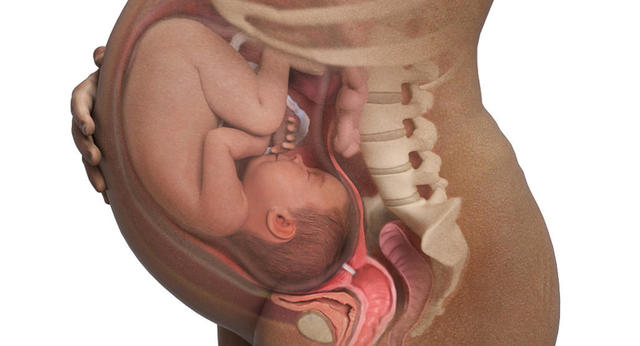

Mantiene una postura que le permite ocupar menos espacio: la cabeza hacia abajo, los brazos cruzados sobre el pecho, las piernas elevadas y dobladas. Es lo que se conoce como postura fetal.

Cuando sus pulmones se encuentran maduros segregan una proteína al líquido amniótico que altera la producción de las hormonas: la placenta reduce lentamente la producción de progesterona y aumenta la oxitocina, que es la que produce las contracciones del útero.

• Semana 40 - Termina Tercer Trimestre - Hora del parto

Semana 40 - Termina Tercer Trimestre - Hora del parto

Ahora el bebé pesa alrededor de 3 o 3,5 kilos y su longitud oscila entre los 49 y los 53 centímetros. Tiene unas uñas muy largas.